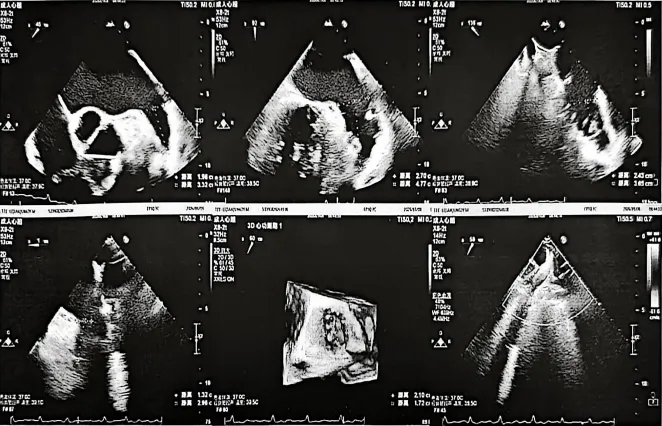

术前超声

左房前后径:49mm

左室舒张末径:58mm

LVEF:58%

术前食道超声测量:

0°开口约13mm、深度29mm

45°开口约19.6mm、深度33mm

90°开口约27mm、深度47mm

135°开口约24mm、深度36mm

左心耳、左心房内未见明显异常回声